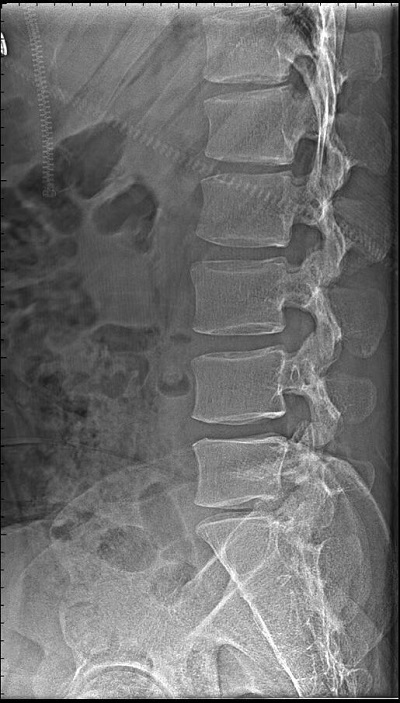

DR影像簡介:直接數(shù)字平板X線成像系統(tǒng),應用于:臨床醫(yī)學,影像部份能夠上下、左右移動,對全身骨骼、心血管、呼吸系統(tǒng)、五官、神經(jīng)系統(tǒng)進行高質(zhì)量拍片。

DR通俗來講就是數(shù)字化的X射線,X光是傳統(tǒng)的影像學檢查手段,主要用于一些的初步篩查。與傳統(tǒng)的X線機相比DR的輻射非常小,還可以進行后期處理分析。

優(yōu)點:作用廣、快捷、價廉。如呼吸科明確是否有肺部病變,骨科用來判斷是否骨折、消化科查看是否有腸梗阻等都可以用X光檢查。

缺點:受制于深淺組織的影像相互重疊和隱藏,有時需要多次多角度拍攝X光片才能看清。DR設備有哪些使用注意事項?DR是一種十分與相當貴重的儀器,在日常的生活應用中還需要結(jié)合其實際的使用性能進行良好的維護和保養(yǎng),并結(jié)合其實際的情況分析故障出現(xiàn)的原因。具體而言,應該注意以下問題: